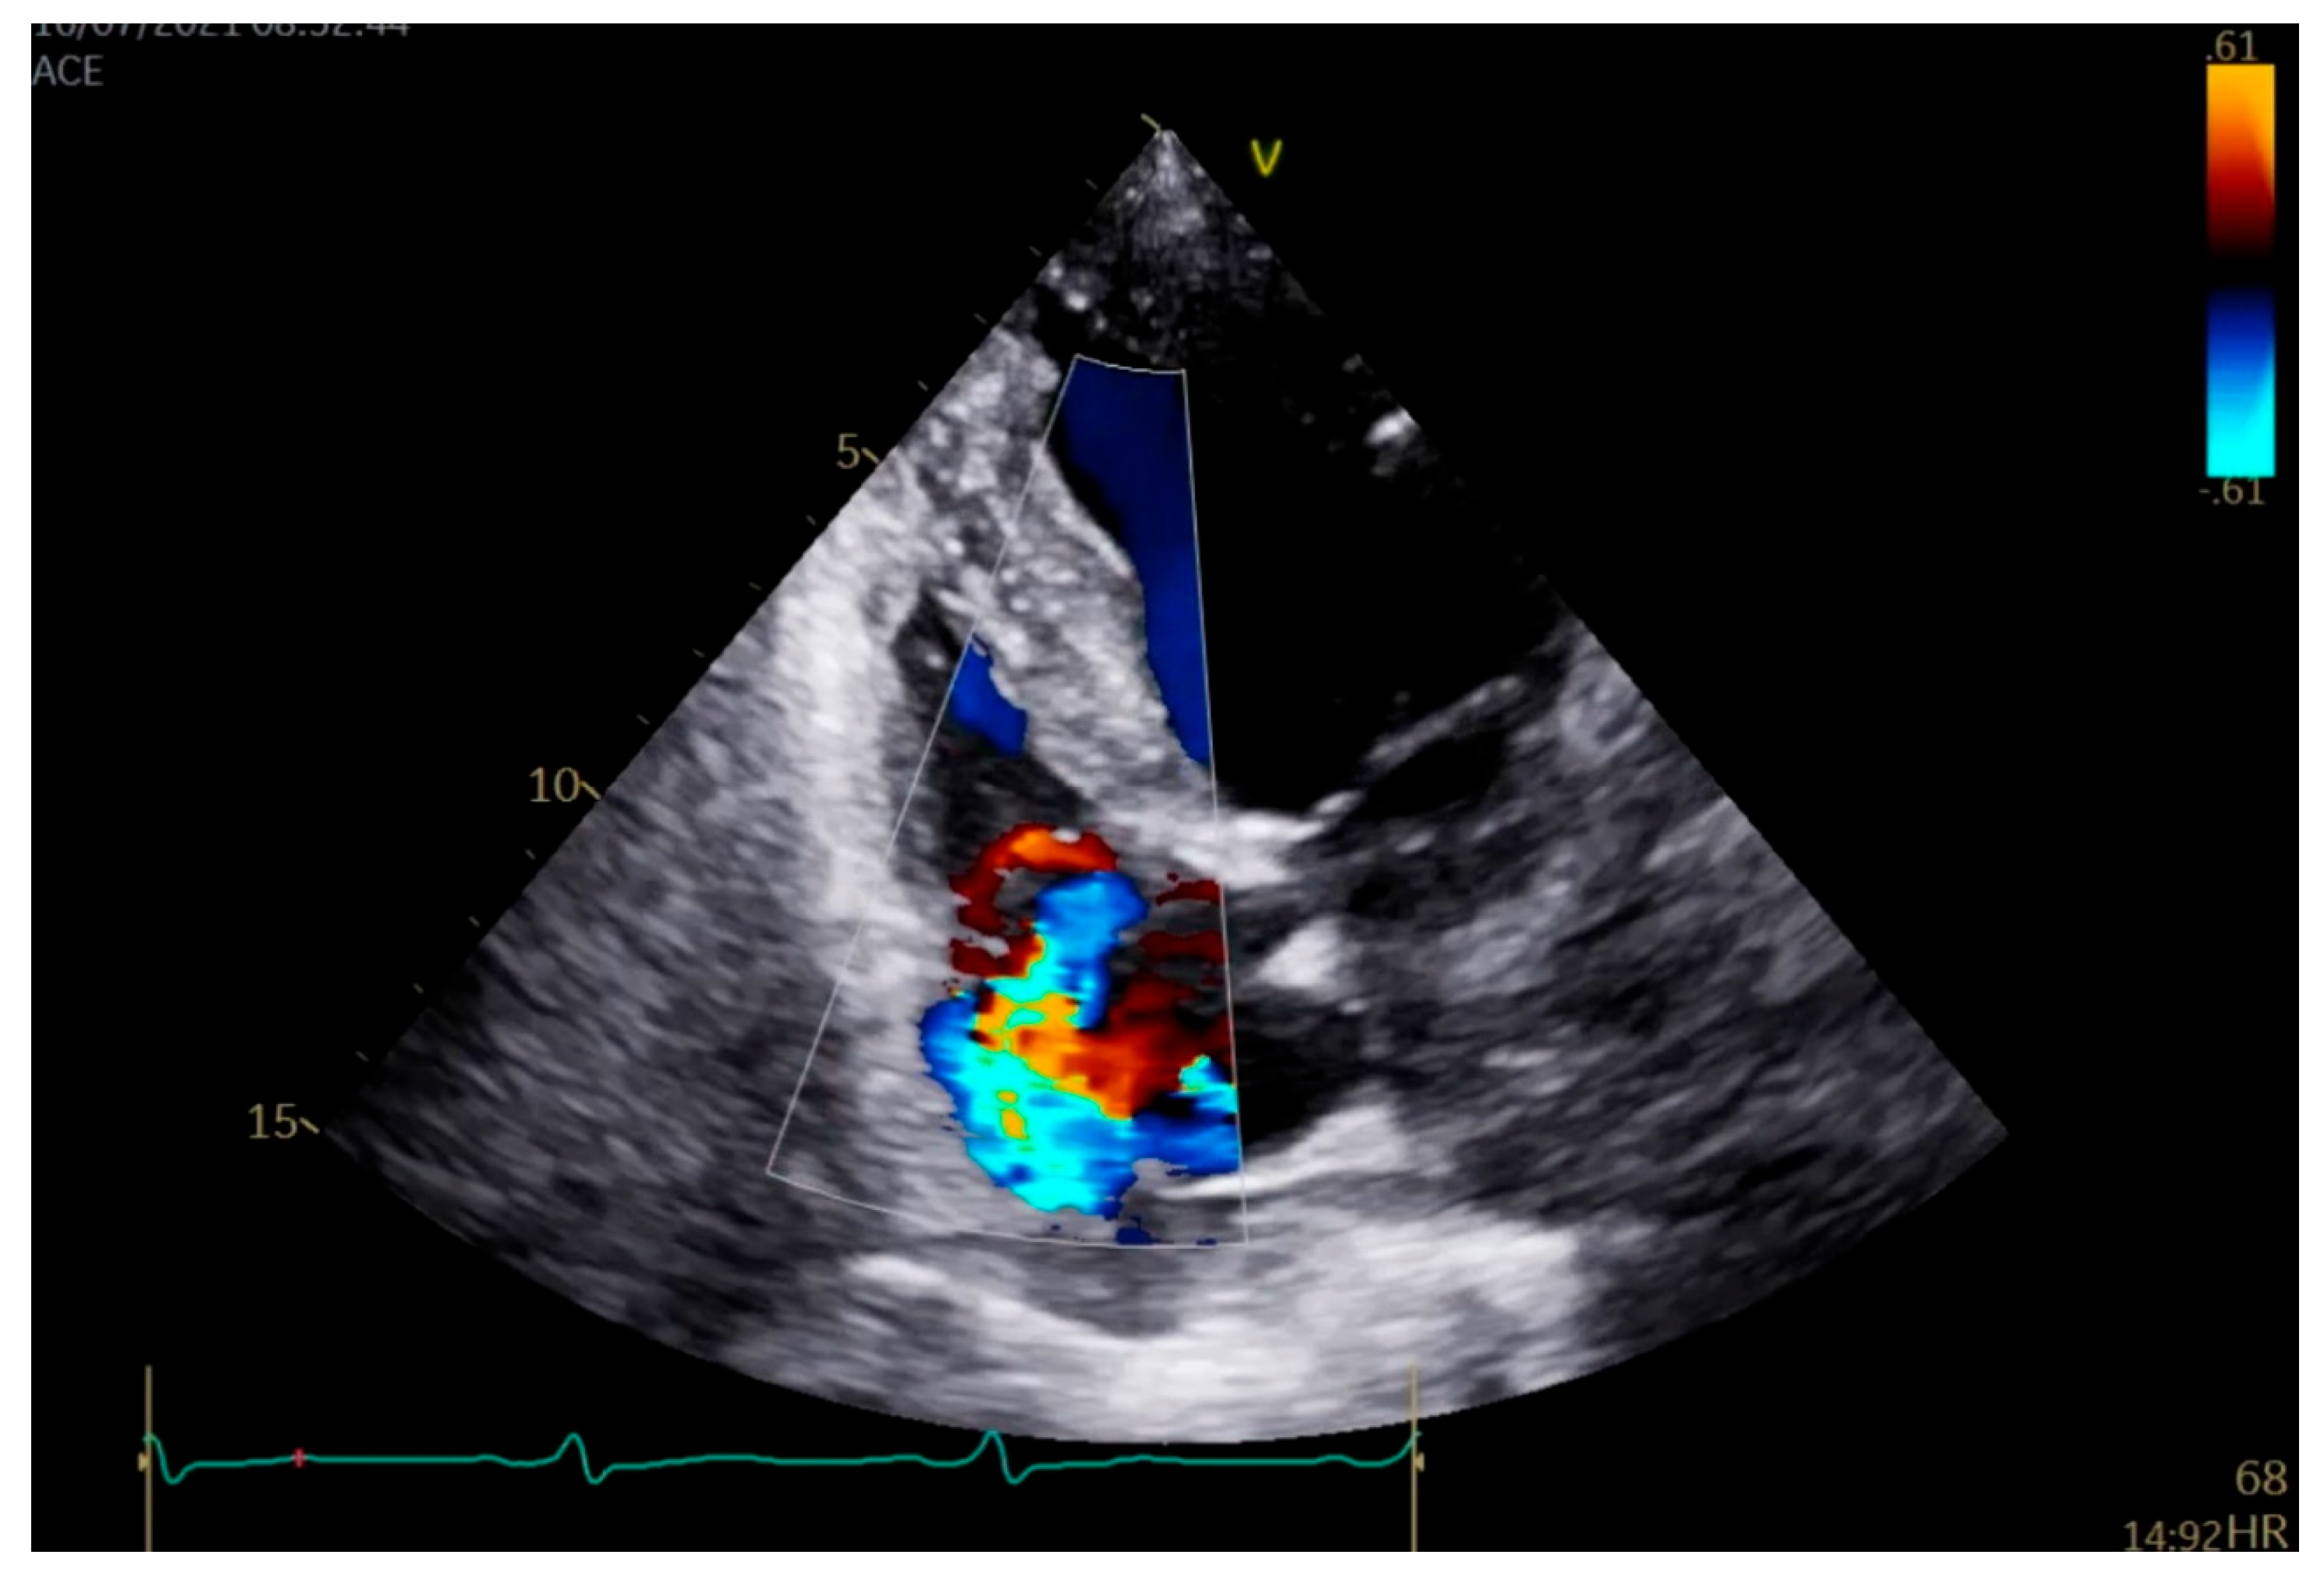

2. Case Presentation